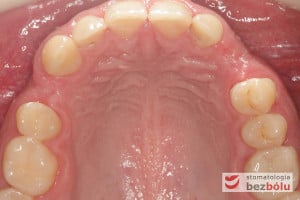

Młody pacjent w wieku lat 28 po wstępnym rozpoznaniu, ze zdiagnozowanym złamaniem kła zarówno górnego jak i dolnego, został skierowany na terapię implantoprotetyczną, prowadzoną przez lekarza dentystę Marcina. W świetle braku możliwości wykonania ekstruzji ortodontycznej i zachowawczego podejścia do leczenia, podjęto decyzję o usunięciu obu zębów, zastosowaniu ułatwiającej gojenie procedury A-PRF i przygotowaniu pacjenta do zabiegu implantologicznego, dodatkowo uzupełnionego o wprowadzenia implantu w miejscu braku zębowego w pEdytujozycji pierwszego przedtrzonowca w szczęce po stronie prawej.

Po zakończeniu procesu gojenia wyrostka zębodołowego, wykonano diagnostykę radiologiczną z zastosowaniem tomografii wiązki stożkowej (CBCT) w celu oceny ilości oraz jakości tkanki kostnej, zarówno w miejscach poekstrakcyjnych, jaki i w pozycji górnego prawego przedtrzonowca. Ponadto pobrano wyciski, oddające sytuację kliniczną w jamie ustnej pacjenta, który zdecydował się na metodę implantacyjną, wykorzystującą nawigację komputerową, z zastosowaniem protokołu MGuide firmy MIS. Procedura ta polega na cyfrowym zaplanowaniu pozycji implantów, a następnie wykonaniu w technice druku 3D szablonu chirurgicznego.Taka metoda pozwala wyeliminować konieczność odwarstwiania płatów, zmniejszając przy tym pozabiegowe dolegliwości. Usprawnia jednocześnie pracę operatora, dokładnie pozycjonując wszczep w pożądanej pozycji. Kolejnym krokiem było przesłanie skanów modeli gipsowych oraz tomografii do siedziby MCenter w Berlinie, gdzie wysoko wyspecjalizowani technicy, dysponujący najnowszą technologią cyfrową, precyzyjnie wykonali szablony nawigacyjne, stosowane podczas zabiegu implantologicznego.